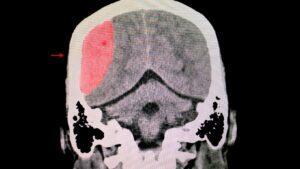

Catastrophic injuries are some of the most devastating types of injuries that anyone can experience, causing significant physical and emotional pain for the victim and their families. These injuries can range from severe brain damage and spinal cord injuries to amputations and severe burns. The effects of these injuries can be long-lasting and may require …

Catastrophic injuries are severe and often life-altering, significantly impacting an individual’s health, independence, and quality of life. These injuries typically result from sudden, unexpected events and can have long-term implications for the affected person and their loved ones. This blog delves into various types of catastrophic injuries, their causes, and the profound effects they have …